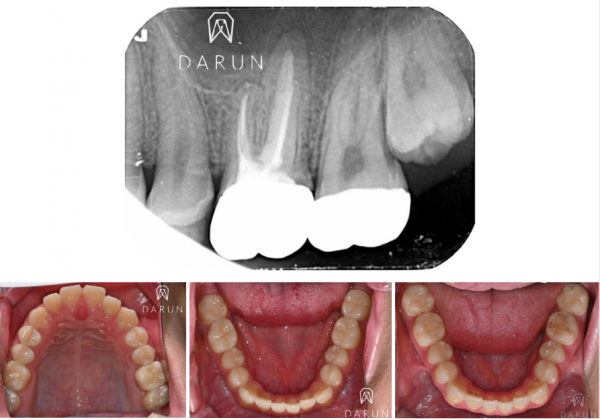

크라운 위한 준비 후 한 컷.

표시된 것처럼 심상치 않은 느낌이에요.

파라색으로 표시한 부분처럼.

치아뿌리 안쪽 관에 비어있는게 많은 것 처럼 보여요.

오염물질! 보철물에서 sealing이 중요하다고 했었죠.

신경치료도 마찬가지입니다.

Sealing이 중요해요.

어떻게 든 Bacteria 침입을 막기 위한거죠.

레진으로 덮여있던 곳을 조심스레 다 제거했더니,

이제 신경치료 흔적들이 나오기 시작합니다.

왜 검냐구요?

Contamination 된 것들은

갈색 혹은 검은색을 띄게됩니다.

이제 신경뿌리 관따라서

오염 된 것들을 전부다 제거해야 합니다.

조금씩 제거할때마다,,

이렇게 오염물질이 계속 나옵니다.

청소 후 모습입니다. 아주 많이 좋아졌어요.

이제 치료 마무리 준비중입니다~

한 근관 오염이 너무 심해서,

일반적으로 쓰는 Gutta percha 재료만으론 한계가 있어서,

여러종류 의 MTA를 함께 이용했습니다.

오염된 부분들이 eradicate 이면 좋겠지만,

잘 정리되었단 사인도 보이네요